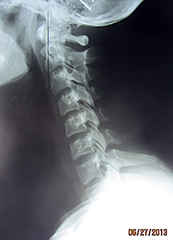

Fig. 1: A-P Open Mouth

In Figure 1, we can see significant imbalances. Many of these imbalances originate from the imbalances found in the feet and can be seen on the digital foot scan (Figure 2). Remember, the body is a compensatory mechanism and any disturbance between atlas, axis and the occiput are typically a compensation for the imbalances below. Therefore, for maximum biomechanical potential, you must address the feet imbalances first.

In Figure 1, we can see there is rotation of the axis, however, the right pillar of the atlas is wider than the left pillar of the atlas because the atlas, too, is rotated and the right pillar is closer to the tube. Finally, if you notice the open mouth, it too, is angled to the left, showing abnormal rotation in the occiput, atlas and axis.